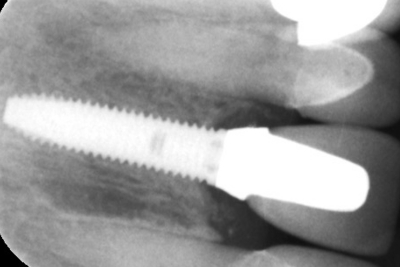

Zubni implant je najčešće specijalno dizajniran cilindrični šraf sačinjen od titana, koji nadoknađuje nedostajući prirodni koren zuba. Implantati sačinjeni od cirkonijumoksida se takođe nekada koriste.

Kontakt implantata i vilične kosti je direktan, bez prisustva vezivnog tkiva. Zbog fiziološkog procesa zarastanja i oporavka kosti, nakon implantacije predstoji period integracije implanata za viličnu kost. Osam nedelja u donjoj i oko šesnaest u gornjoj vilici. Ukoliko je primenjena i procedura nadogradnje kosti period integracije može se produžiti za nekoliko nedelja.

Stepen uspešnosti terapije implantatima na 10 godina je oko 97 procenata. Preostala 3 procenta se najcešće izgube posle same ugradnje usled više razlicitih faktora. Preduslov za uspeh je da se pacijent pridržava saveta stomatologa, redovno održava oralnu higijenu, redovno dolazi na kontrolne preglede i profilaktičke tretmane. Jednom kvalitetno integrisan implantat teško je ukoniti nehirurškim putem i zato je planiranje njihove postavke krucijalna faza uspešnog tretmana.